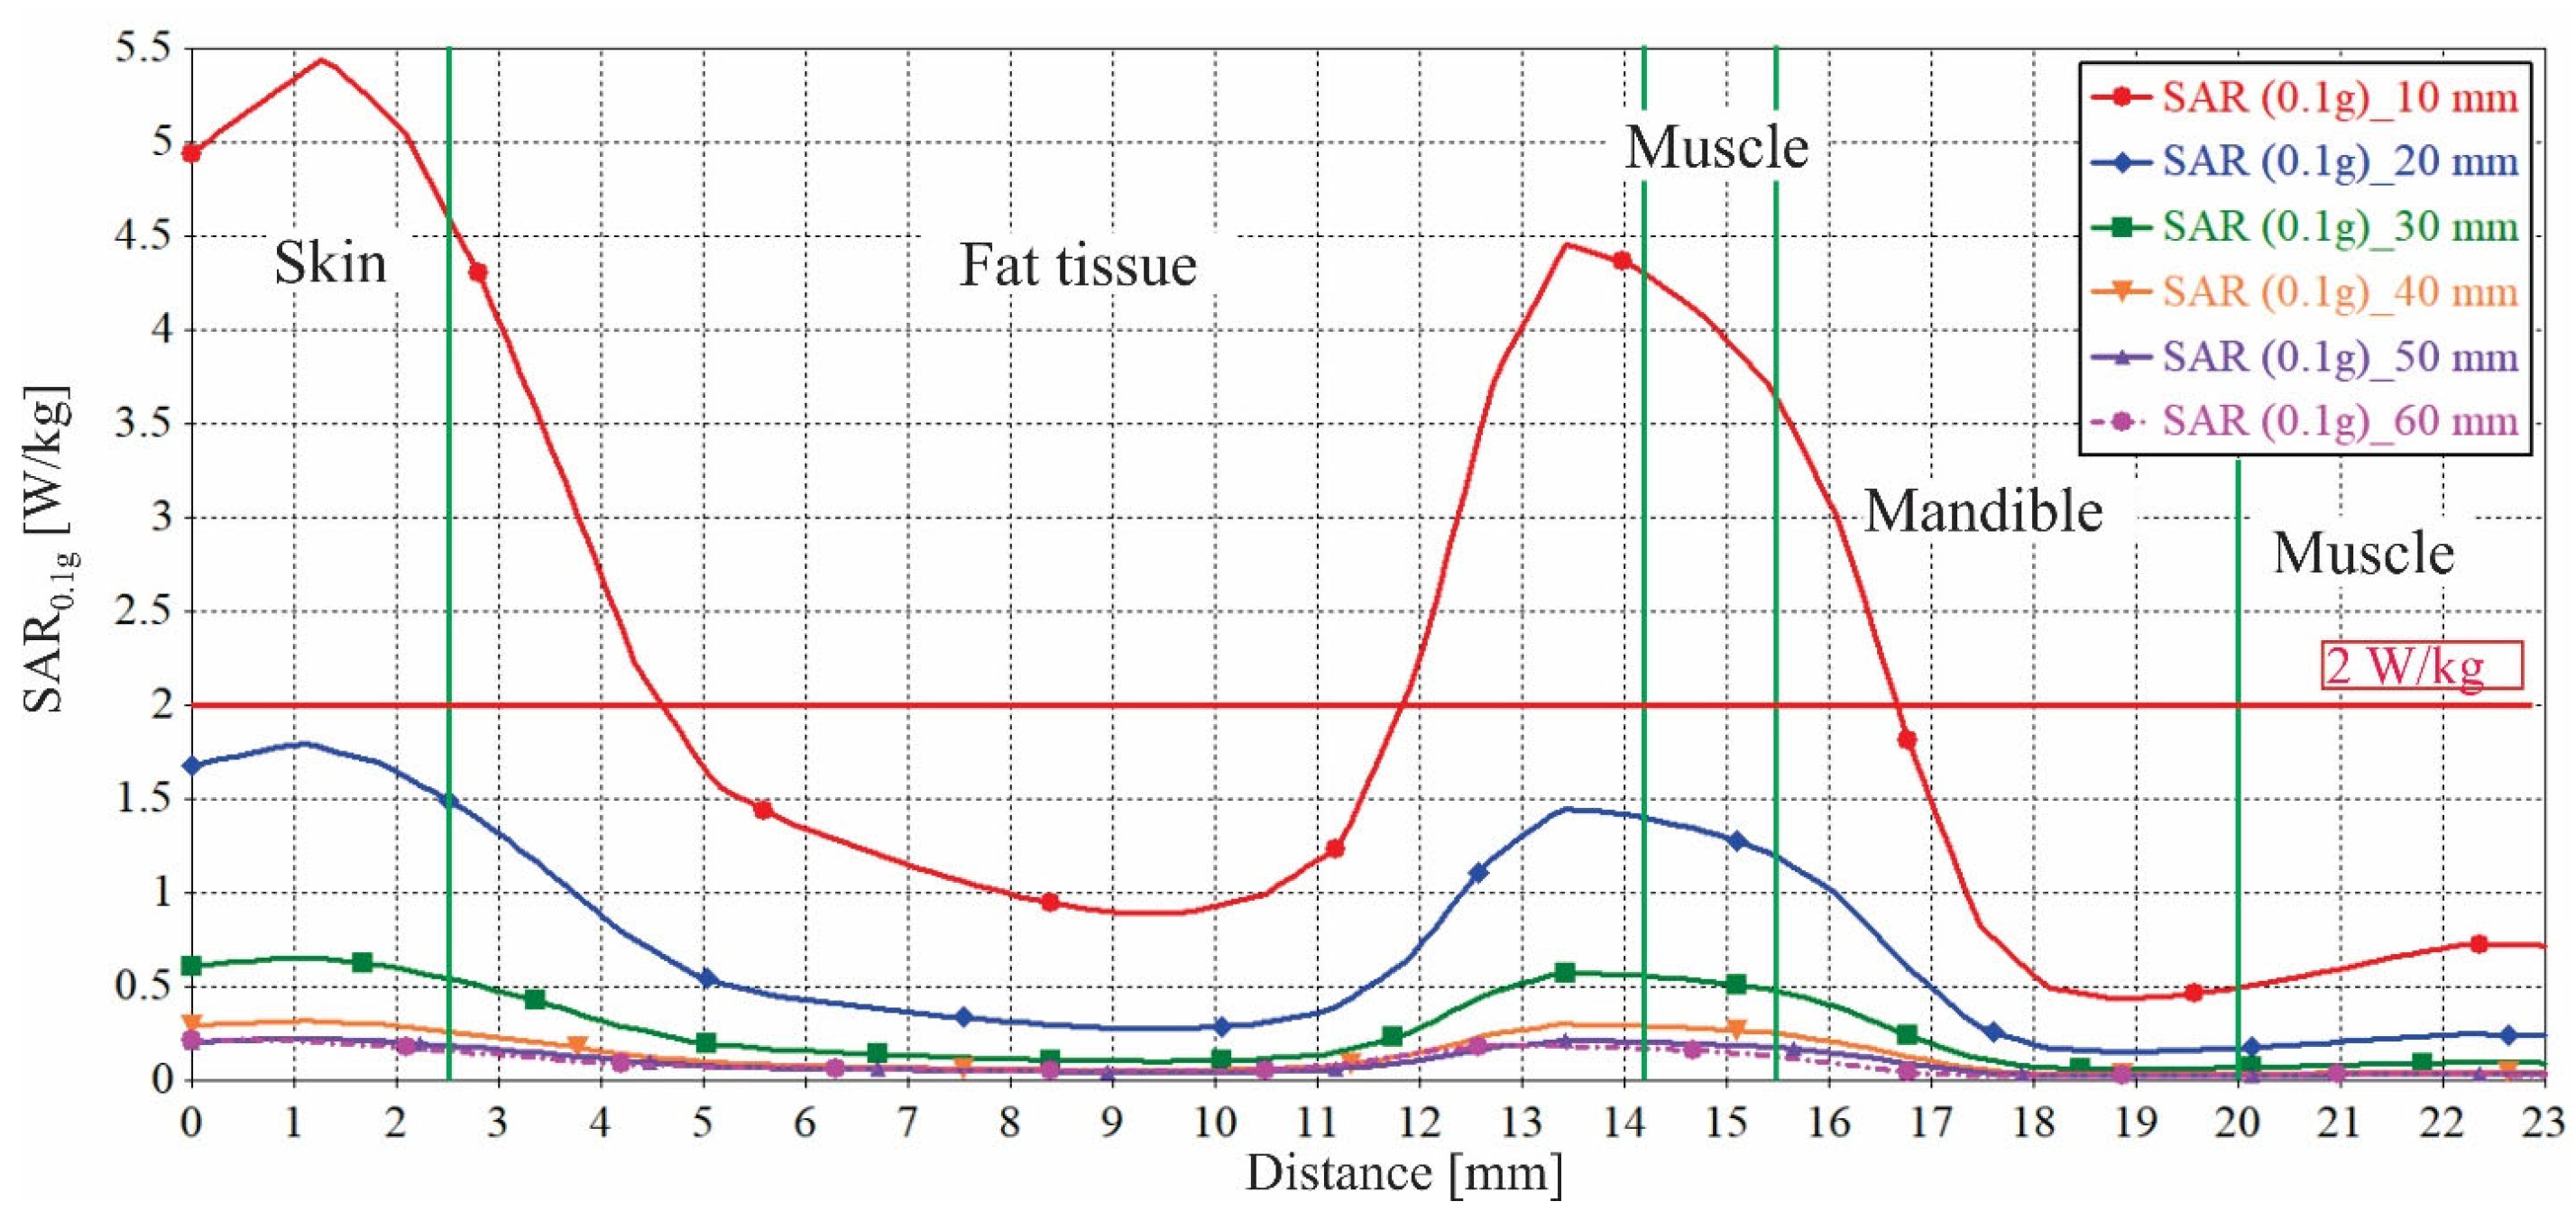

3.3. Impact of the Face-to-Phone Distances on the Electric Field and SAR Distribution in the Implant Vicinity